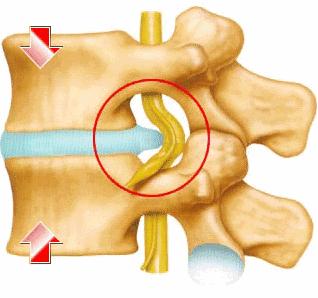

腰椎间盘突出症是骨科常见的疾病之一,本病主要是由于腰椎间盘各部分(髓核、纤维环及软骨),尤其是髓核,存在不同程度的退行性改变后,在年龄增长、劳损或外力的作用下,椎间盘的纤维环破裂,髓核组织从破裂之处突出(或脱出)于后方或椎管内,导致相邻的组织如脊神经根、脊髓、马尾等遭受化学刺激或物理性压迫,进而表现出腰骶部酸痛、下肢疼痛、麻木,甚至大小便*禁失**、双下肢无力等一系列神经症状。

椎间盘突出可分为哪些类型?

膨出型

纤维环未破裂,膨出为生理退变,纤维环松弛但完整,髓核皱缩,表现为纤维环均匀超出椎体终板边缘。

突出型

纤维环破裂,后纵韧带完整。髓核经纤维环裂隙向椎管内突出,后纵韧带未破裂,影像学表现为椎间盘局限性向椎管内突出,可无症状,部分患者出现典型神经根性症状、体征。此型通过牵引、卧床等保守方法可缓解,但由于纤维环裂隙愈合能力较差,复发率较高。

脱出型

纤维环、后纵韧带均破裂;纤维环、后纵韧带完全破裂,髓核突入椎管内多有明显症状体征,脱出多难自愈,保守治疗效果相对较差,大多需要微创介入或手术治疗。

游离性

脱出的髓核在椎管内游走。脱出髓核与相应椎间盘不连接,可游离到椎管内病变的上或下节段、椎间孔等,其临床表现为持续性神经根症状或椎管狭窄症状,少数可出现马尾神经综合征,此型常需手术治疗。